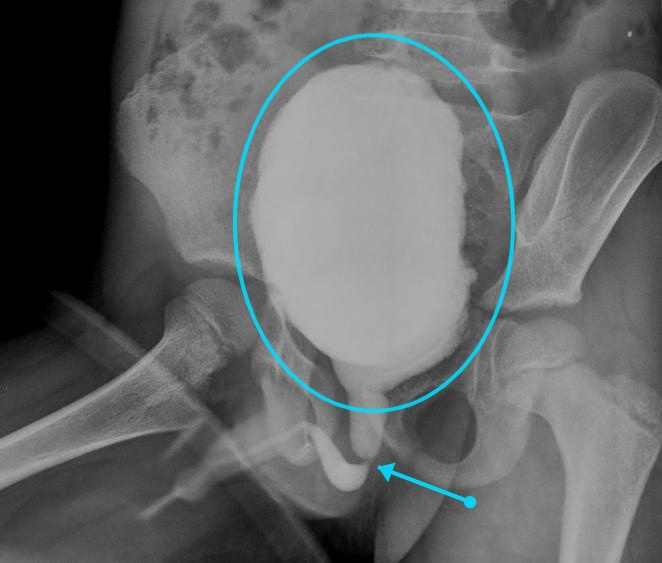

Puzzle 67

Puzzle 67 annotated

What's the Diagnosis?